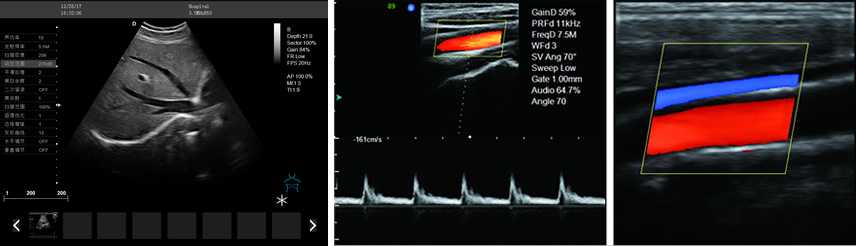

彩色多普勒

產品性能:高集成數字式彩色多普勒技術,寬頻探頭,強勁的組合式模塊化軟件設計,全數字式大容量圖像存貯和文件歸檔管理,適用范圍:用于人體超聲診斷檢查。